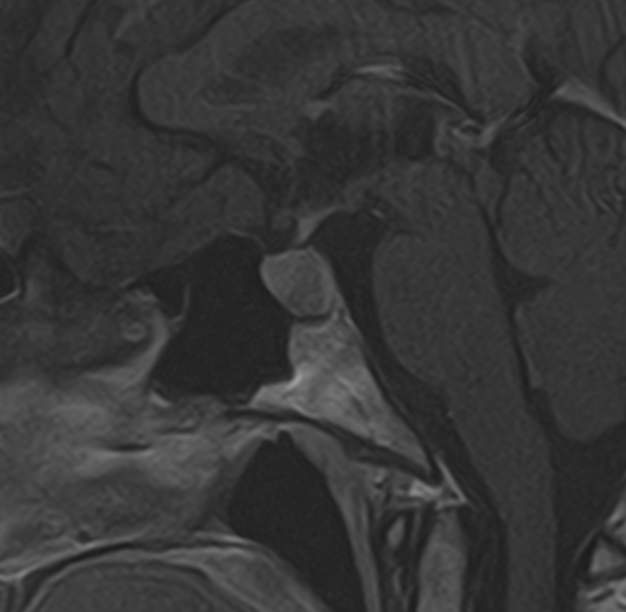

Для выявления опухолевых образований гипофиза проводится МРТ гипофиза с контрастным усилением. Для этого пациенту внутривенно вводится препарат, содержащий контрастное вещество, имеющее в своем составе металл гадолиний. Контрастное вещество избирательно накапливается в патологических очагах, интенсивность этого накопления можно оценить визуально, а также с помощью компьютерной программы — в цифровом выражении.

Метод позволяет создавать детализированные изображения области турецкого седла и является лучшим способом диагностики любых объемных образований гипофиза. С помощью МРТ гипофиза можно выявить макроаденомы и большинство микроаденом гипофиза размером от 1 мм.

В клинике «Доступная медицина» проводится МРТ гипофиза с контрастом на современном высокопольном томографе TOSHIBA VANTAGE TITAN 1,5 Тесла. Индукция магнитного поля 1,5 Тесла обеспечивает высокую четкость изображения и отвечает мировым стандартам качества диагностики заболеваний центральной нервной системы.